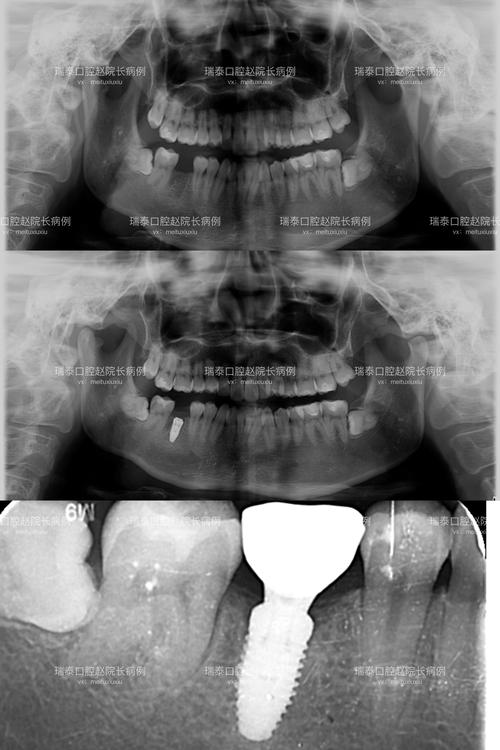

- 术后评估: 种植手术后,有时需要CT来评估种植体的位置、角度、深度是否理想,以及与重要的解剖结构(如下牙槽神经管、上颌窦)的关系。

- 种植体周围炎的诊断: 当怀疑有种植体周围炎(种植体周围的软硬组织炎症)时,CT可以帮助评估骨吸收的程度和范围,尽管伪影会干扰细节观察,但结合临床检查和其他影像(如根尖片)仍能提供重要信息。

- 其他影像学检查: 对于常规的种植体随访,有时会使用根尖片或全景片,这些检查伪影较小,但显示细节(尤其是三维结构)的能力远不如CT,它们通常用于观察种植体整体位置和骨高度的大致情况,而非精细评估骨结合或微小病变。